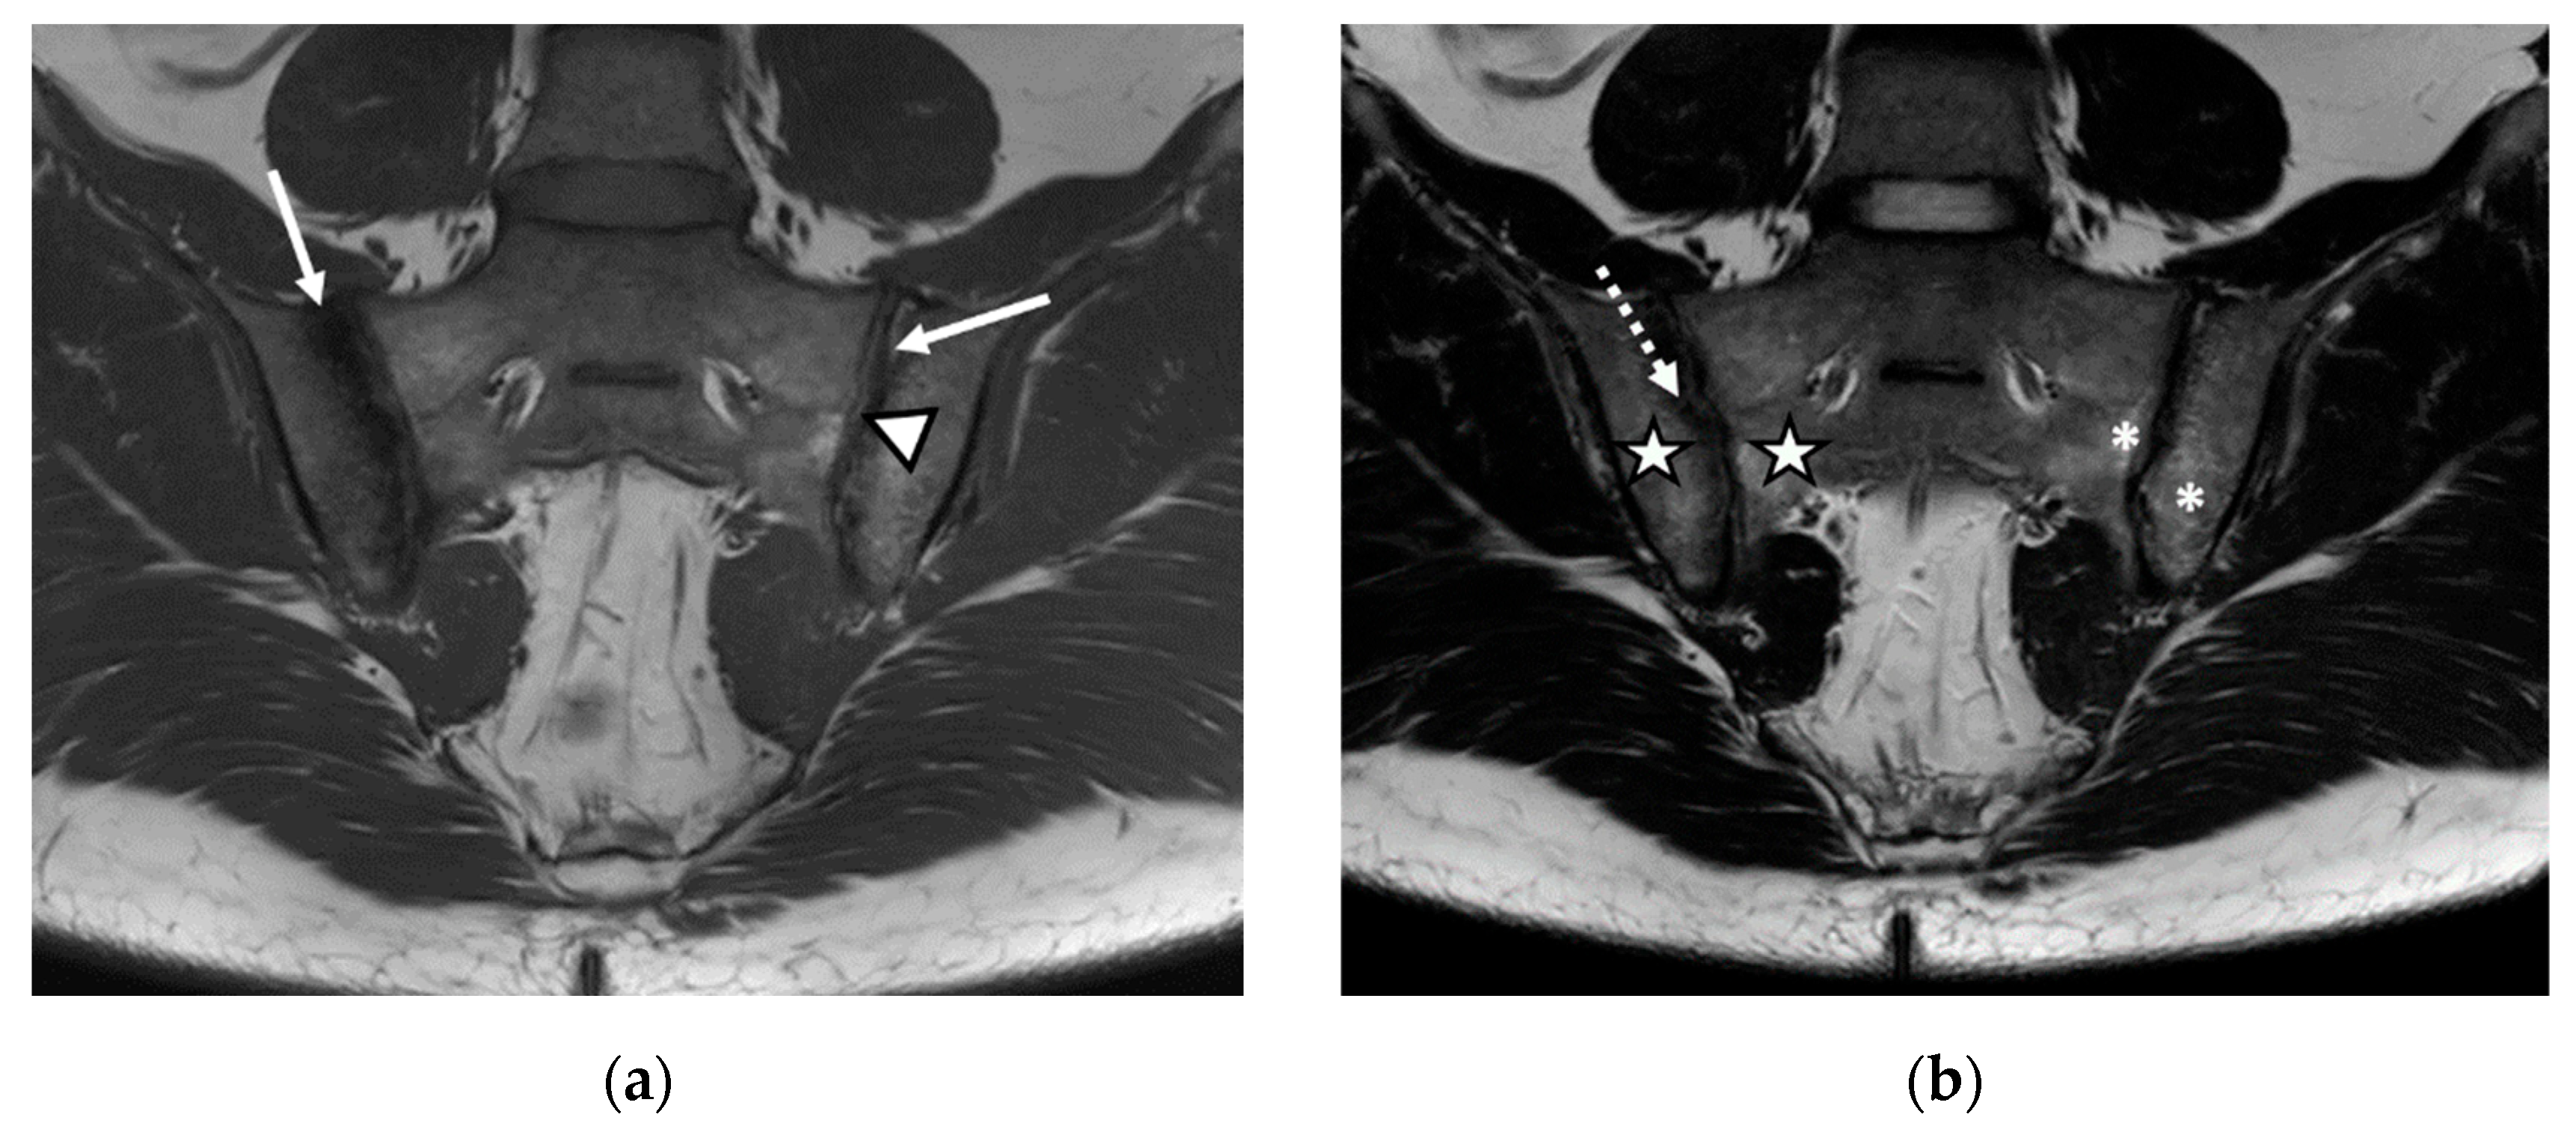

We evaluated 68 sacroiliac joints. The prevalence of MRI-detected abnormalities is presented in Table 2. The results of the SR were considered as the reference data. Inflammatory and structural changes were detected on the MRI sequences of the sacroiliac joints. The most frequently encountered inflammatory change, both on the left and right sacroiliac joint, was the presence of bone marrow edema (44.11–58.82%), followed by enthesitis (17.64–26.47%) and synovitis (11.76–17.64%). Regarding structural changes, the most prominent was subchondral sclerosis (50–59.37%), followed by erosions (35.29–41.17%), joint space narrowing (38.23%), fat metaplasia (17.64–23.25%), and backfill (11.76–20.58%) (Figure 1, Figure 2 and Figure 3).

Figure 3.

The MRI aspect of the sacroiliac joints included pseudo-widening of both sacroiliac joints, with marked bone marrow edema (star) of both the sacrum and the right iliac bone, in the proximity of the ipsilateral sacroiliac joint space, right iliac bone erosions (discontinuous arrow), bilateral subchondral sclerosis (continuous arrow), and fat metaplasia (asterisk), affecting the left iliac bone, and the left part of the sacrum and backfill (arrowhead) of the left sacroiliac joint space: (a) T1-weighted sequence; (b) T2-weighted sequence (without fat suppression); (c) STIR sequence.